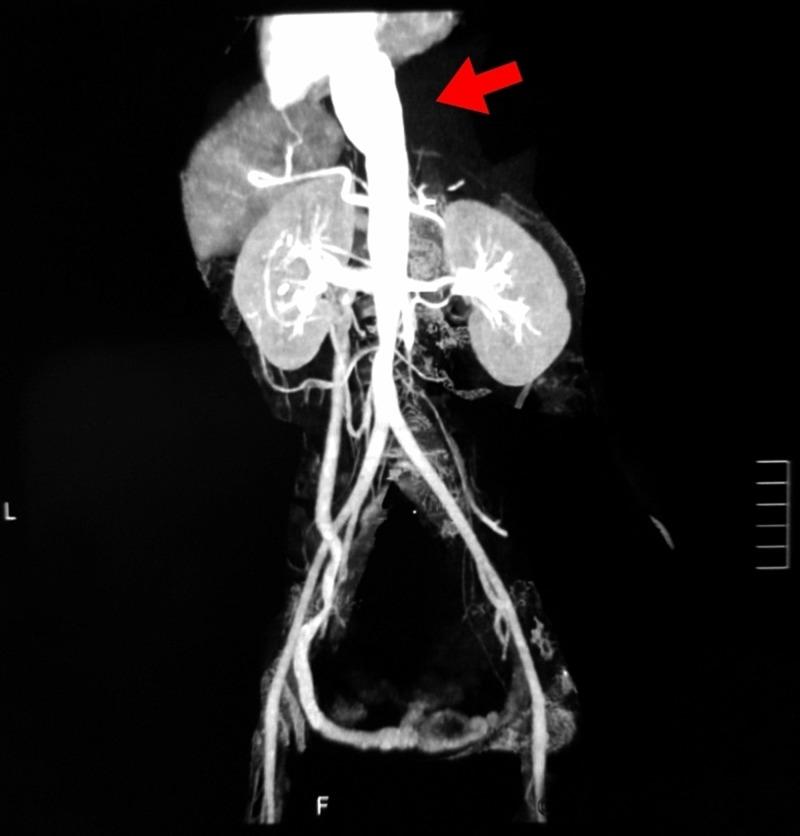

Takayasu arteritis (TA) is a chronic inflammatory large-vessel vasculitis of the aorta and its major branches. It is a relatively rare disease, which presents with a wide spectrum of clinical features. Back pain is, however, rarely described to be a presenting symptom of TA. We report a case of a 28-year-old female with no known co-morbidity, who presented with back pain along with intermittent fever, dry cough, and significant weight loss. After an extensive inpatient workup, a computed tomography (CT) scan with contrast of chest and abdomen revealed evidence of vasculitis involving aorta, common carotid arteries, renal arteries, common iliac arteries as well as external and internal iliac arteries. A confirmatory CT abdominal aortography established the diagnosis of TA. The patient was treated with long-term oral corticosteroid therapy. Our case highlights that while assessing nonspecific back pain with elevated inflammatory parameters, particularly in young women, TA should be considered as one of the differential diagnoses.

高安动脉炎(TA)是一种累及主动脉及其主要分支的慢性炎症性大血管血管炎。它是一种相对罕见的疾病,临床表现多样。然而,背痛很少被描述为TA的首发症状。我们报告一例28岁女性,无已知合并症,以背痛伴间歇性发热、干咳和显著体重减轻就诊。经过全面的住院检查,胸部和腹部增强计算机断层扫描(CT)显示有血管炎累及主动脉、颈总动脉、肾动脉、髂总动脉以及髂内外动脉。腹部主动脉CT血管造影确诊为TA。该患者接受了长期口服糖皮质激素治疗。我们的病例强调,在评估伴有炎症指标升高的非特异性背痛时,尤其是在年轻女性中,应将TA列为鉴别诊断之一。